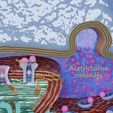

神经肌肉接头示意图

/https://fbi.cults3d.com/uploaders/27147996/illustration-file/bcbce364-66a9-4332-bcbb-837c112eb2f1/p3.jpg)